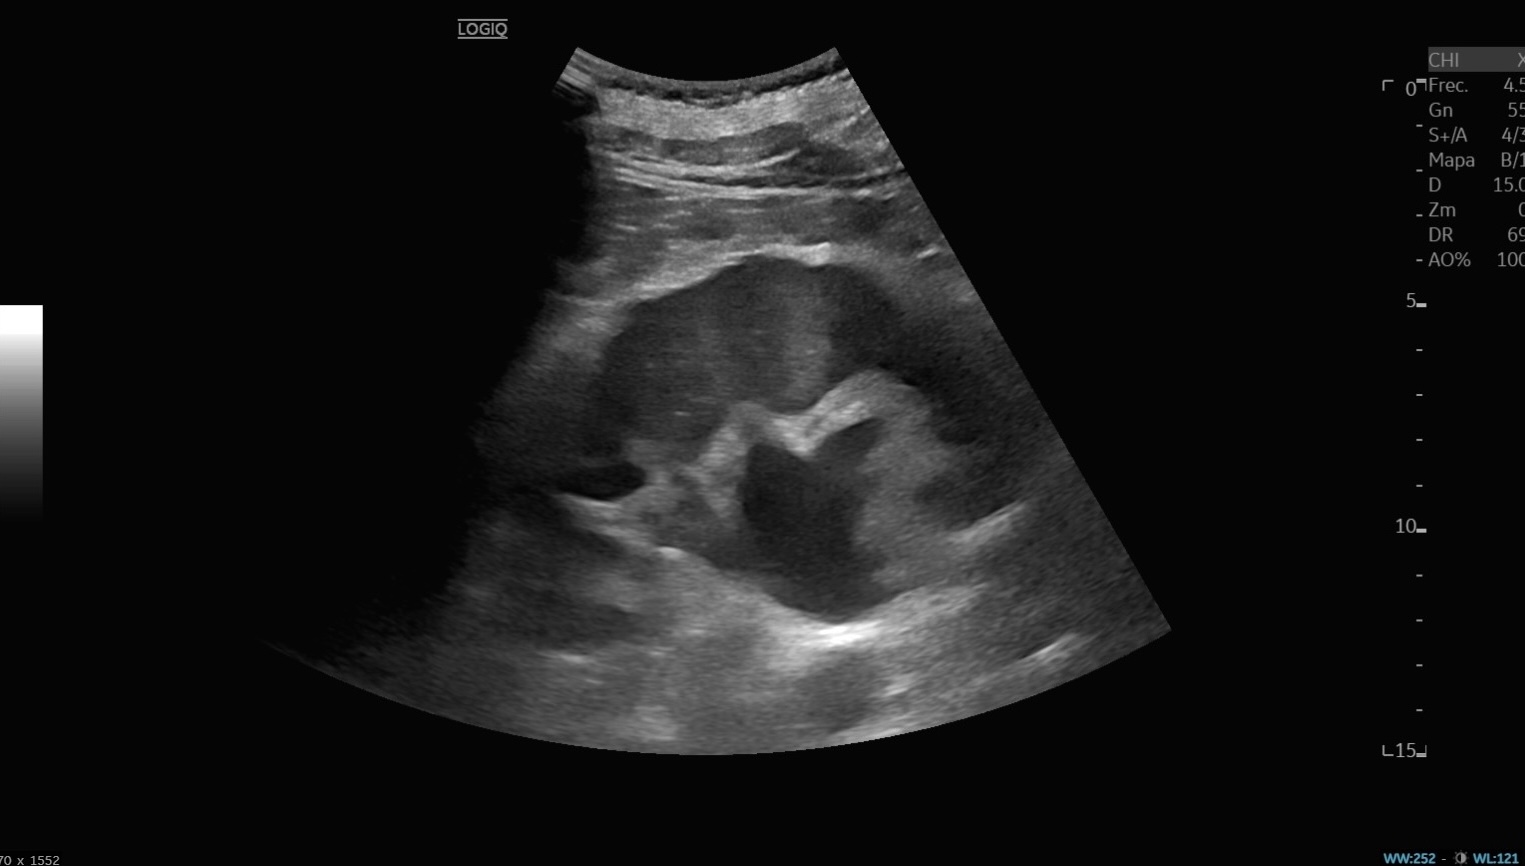

Ecografía abdominal: vejiga hiperdistendida con unos 3000 ml de orina y hidronefrosis bilateral moderada-severa, sin lesiones intravesicales ni causa obstructiva aparente. Analítica: anemia microcítica (Hb 9 g/dl), insuficiencia renal aguda grave (urea 409, creatinina 14,2), acidosis metabólica (pH 7,26; HCO₃ 6,3), PCR 19,7. Sedimento urinario positivo para infección.

Por el cuadro constitucional y vómitos, la primera sospecha fue neoplasia maligna. Sin embargo, la ecografía reveló retención urinaria masiva con afectación pielocalicial bilateral, orientando el diagnóstico hacia insuficiencia renal aguda obstructiva.